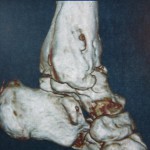

Εικόνα 3 α,β,γ

Προεγχειρητική τρισδιάστατη αξονική τομογραφία της ποδοκνημικής άρθρωσης.

Παρατηρείται σαφής καταστροφή της άρθρωσης.